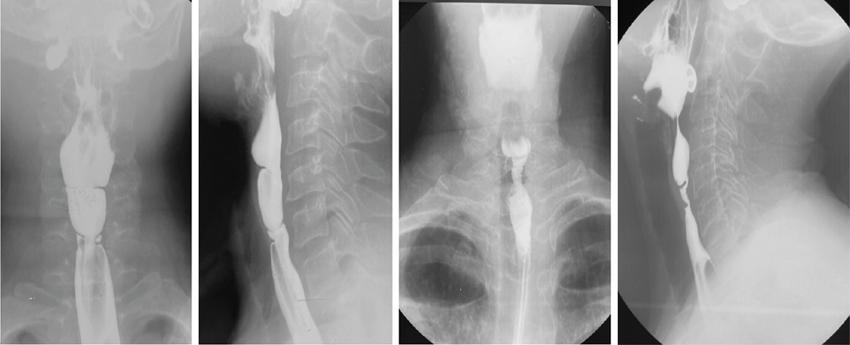

Barium swallow (13 mm tablet/marshmallow/bread soaked in barium) with video fluoroscopy

Inexpensive, easily available

Appropriateness limited on use of spot images and by proficiency/experience of technician/doctor

Can be tailored depending on patient presentation

Negative barium study does not rule out need of endoscopy

Video-fluoroscopy allows adequate/physiological assessment of oesophageal motility

No cross-sectional information obtained

Barium is not absorbed and hence allergic reactions are rare

Barium can elicit severe mediastinitis when used in oesophageal perforations